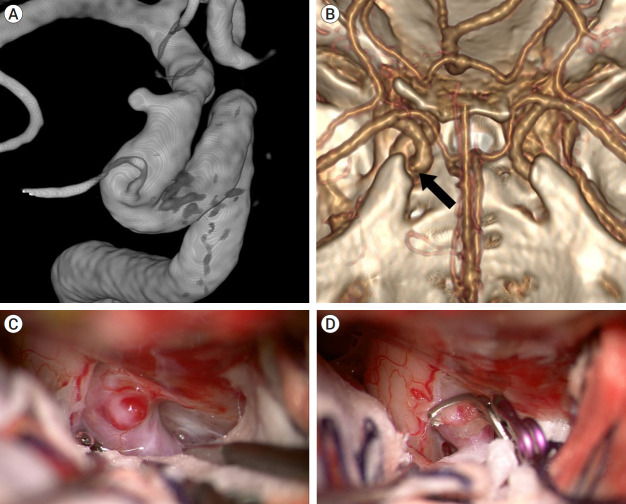

Methods: Between 2017 and 2022, 25 patients with unruptured dorsal ICA aneurysms (less than 4 mm in diameter) underwent microsurgical direct clipping. These cases involved the left ICA (n=17) and the right ICA (n=8), with a mean aneurysm size of 3.3 mm (range, 2.5 to 4 mm). We used computed tomography angiography (CTA) and digital subtraction angiography to elucidate the anatomical relationship between dorsal ICA aneurysms and other structures. All procedures involved an ipsilateral pterional approach with securement of the ipsilateral cervical ICA for proximal control.

Results: Among the 25 dorsal ICA aneurysms, 8 (32%) were clipped without the FL being incised. Another 5 (20%) were clipped solely after the FL was cut. For the remaining 12 cases, the aneurysms were successfully clipped following FL incision and partial ACP removal. Patients exhibited favorable postoperative recoveries with good outcomes, and postoperative CTA revealed complete aneurysm clipping without any residual remnants. Conclusions: We were able to perform clipping without removing the ACP in 13 patients (52%), and in 8 of these (32%), the clipping was carried out directly without cutting the FL. Microsurgery, coupled with proximal control of the cervical ICA, can serve as a viable alternative for patients with small dorsal ICA aneurysms, especially when endovascular treatment options are limited, and 3D CTA confirms a clear anatomical relationship with the ACP.